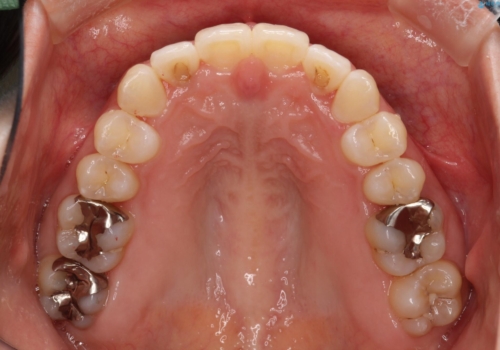

抜歯なし/インビザラインによるマウスピース矯正にて治療を行いました。

内側に入り込んでしまっている歯を出してくることに非常に時間がかかりましたが、一度歯を歯茎の方へ押し込みそして前へ出してくる2段階の治療を行いました。

見た目、噛み合わせ及び、治療期間や施術内容に大変ご満足いただきました。